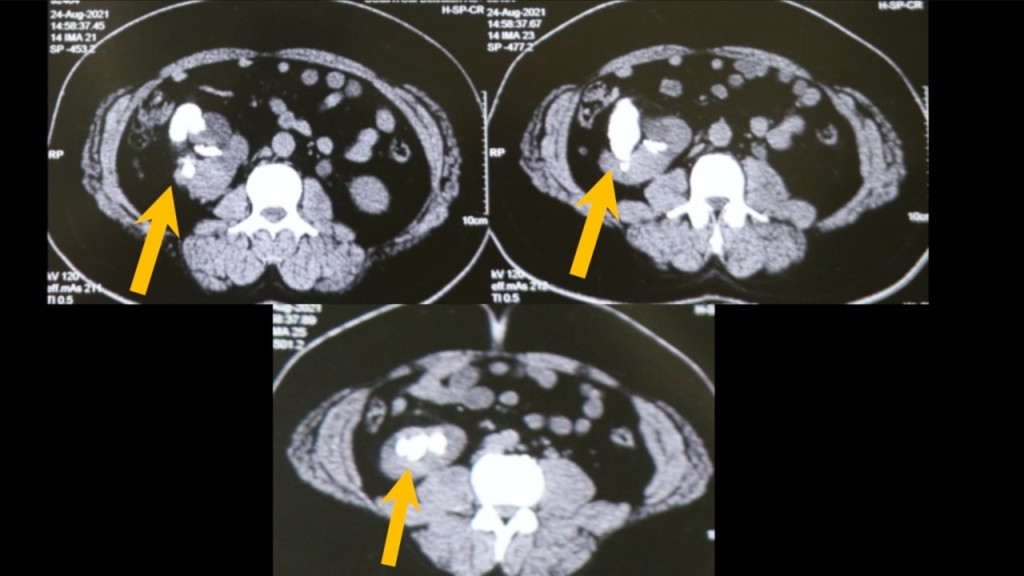

醫生發現病人有大量腎石,兼患有先天性異位腎,手術難度大增。互聯網圖片

患者為一位50歲的教師,因腹痛前往醫院就診,經檢查後發現腎臟中藏有156顆腎結石,此後他亦患有先天性異位腎。醫生評估後,使用腹腔鏡與內視鏡進行手術,耗費3小時才將結石全數取出。

主刀醫生、泌尿科專家莫漢博士表示:「這是我第1次在單個病患身上取出這麼多腎結石。這名病患可能患有腎結石長達2年,只不過一直沒有出現顯著症狀,突發性疼痛迫使他須接受全面性的檢查,才發現腹中藏有大量腎結石」。

莫漢博士補充,「患者患有先天性異位腎,導致腎臟與一般人的正常位置不同,雖腎臟在異常位置並非問題主因,但必定會增加取出結石的難度」。他提到,經審慎評估後,手術團隊決定使用腹腔鏡、內視鏡進行手術,而病人術後已經恢復身體健康,可以正常生活。